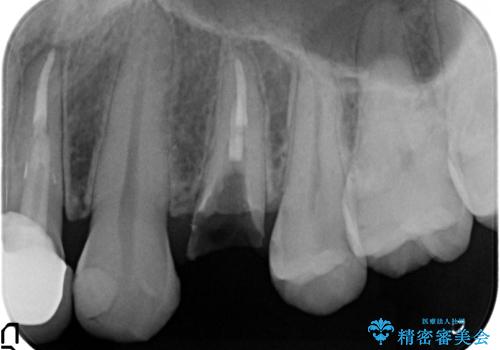

左上4の補綴物を除去したところ縁下歯質だったため、歯牙の挺出を提案し行いました。

挺出終了後は歯肉切除および骨外科により歯周組織を整え、オールセラミッククラウンによる補綴を行いました。

縁下カリエス(歯茎より深い虫歯)の治療について

虫歯が進み歯茎より深くなってしまうと、虫歯を取り残してしまうリスク、樹脂の硬化の妨げ、補綴物の不適合、歯肉炎・歯周病のリスクの増大等様々な弊害が起こり得ます。

そのため当院では歯周外科手術(歯茎を下げる手術)や歯の挺出による、虫歯が歯茎より深いという問題の解決を推奨しております。